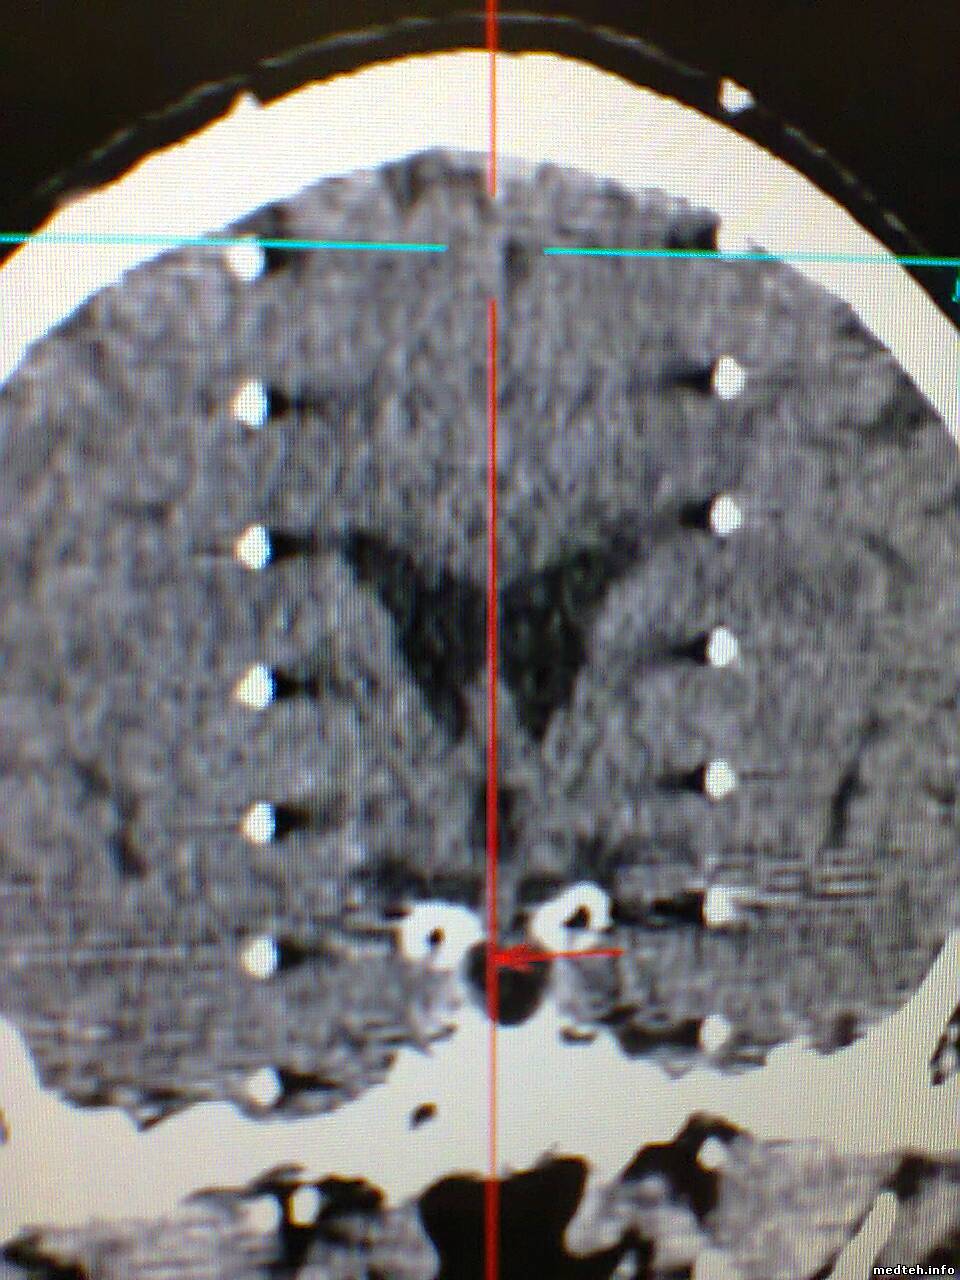

Здравствуйте, появился спиральный артефакт на изображениях, который исчезает примерно на день если провести калибровку по воздуху, думал что дело в модуле датчиков но тест defective channels не показывает ошибок. Что-нибудь кроме датчиков может давать такое изображение? Есть вероятность что детектор как-бы отпаивается? Можно ли тогда запаять его обратно?

Доброго времени! Столкнулся с артефактом который появляется переодически ошибки при этом не даёт . Кто что думает...?

1982181.jpg (228.6 Kb) · 1606727.jpg (311.5 Kb) · 4363118.jpg (258.9 Kb)